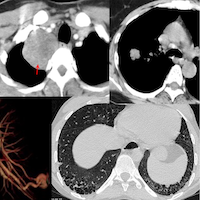

68-years old with a 3-months history of cough and expectoration.

CT scan shows reticular opacities with peripheral distribution and lower lobe predominance with traction bronchiectasis. Is this a fibrosing ILA?. It turns out she had COVID-19 in Sep 2020.

The video describes the case, the comparative findings of the 2020 and 2025 scans and discusses a new best practice paper on describing COVID-19 sequelae.